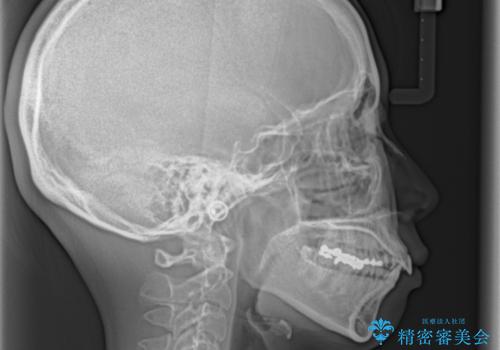

顎先に梅干し皺ができる 閉じにくい唇を抜歯矯正で閉じやすく

- 口元の突出感と口の閉じにくさを気にして来院された患者様です。

上下左右第一小臼歯4本を抜歯し、ワイヤー装置にて口元を引っ込めるよう矯正治療を行うこととしました。

奥歯が前方に傾斜していることで深く咬みこむ(ディープバイト)状態であったので、なかなか抜歯したスペースが閉じず、様々な方法でディープバイトを改善しながら治療を進めていくこととなりました。